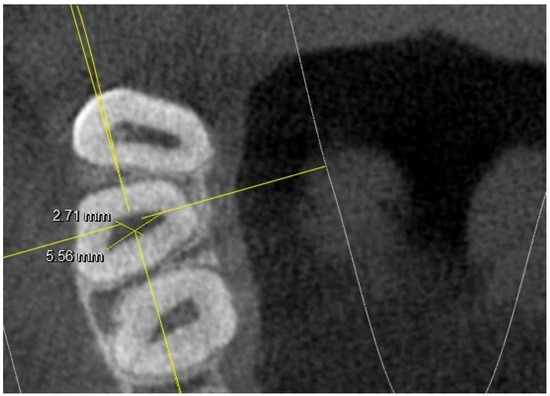

- long and short diameter of the pulp chamber floor;

- diameter of root canal orifices;

- distance between intra- and inter-root canals;

| At the orifice: MB-DB distance | 2.33 | 0.22 | 2.35 | 0.21 | 2.22 | 0.2 | 2.19 | 0.2 | ||

| DB-P distance | 2.96 | 0.44 | 3.25 | 0.2 | 3.32 | 0.41 | 3.67 | 0.2 | ||

| 5 mm from the CEJ: MB-DB distance | 4.35 | 0.82 | 2.88 | 0.62 | 4.13 | 0.78 | 2.97 | 0.64 | ||

| DB-P distance | 5.65 | 1.03 | 5.42 | 1.12 | 5.44 | 1.23 | 5.1 | 0.98 | ||